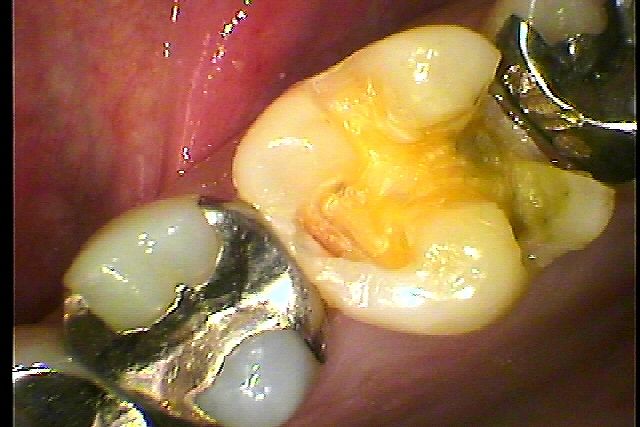

左上銀歯が昨日取れた 診てほしい セレックプライムスキャンを用いた審美治療|お知らせ |広島市安佐南区の歯科医院 左上銀歯が昨日取れた 診てほしい セレックプライムスキャンを用いた審美治療 トップ お知らせ・ブログ お知らせ 左上銀歯が昨日取れた 診てほしい セレックプライムスキャンを用いた審美治療 左上銀歯が昨日取れた 診てほしい セレックプライムスキャンを用いた審美治療 銀歯が取れた歯になります 下に虫歯が存在していました 隣接部にも虫歯があります このように歯の間はむし歯の好発部位になります 近心部、遠心部に虫歯が波及。 歯の隣接部にまで伸ばしていきます セレックプライムスキャンを用いてセラミックを作成していきました Web診療予約 初めての方へ 選ばれ続ける理由 院内設備について 歯が痛いしみる一般歯科 歯がぐらぐらする歯周病 健康な歯を保ちたい予防歯科 子供の虫歯予防をしたい小児歯科 銀歯をセラミックに審美歯科 白い歯を目指しませんか?ホワイトニング 矯正専門医がいるので安心矯正歯科 抜けた歯を補いたいインプラント・入れ歯 医院案内 スタッフ紹介 メリィハウス歯科クリニックオフィシャルホームページ ラベンダー歯科クリニックオフィシャルホームページ お知らせ・ブログ ホーム 診療科目 一般歯科 歯周病治療 予防治療 小児歯科 審美治療 ホワイトニング 矯正歯科 入れ歯・インプラント マウスピース矯正 初めての方へ 院長・スタッフ 設備紹介 医院案内・アクセス メニューを閉じる